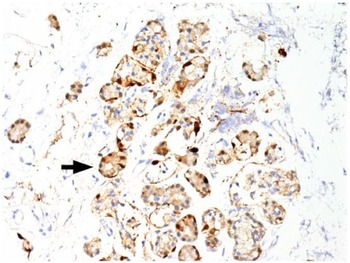

Immunohistochemical staining for pan-cytokeratin AE1/AE3 antibodies demonstrated only very focal residual attenuated surface epithelium (Figure 4). There was strong nuclear and cytoplasmic positivity for S100 immunostain in scattered cells within structures, compatible with Bowman's glands (Figure 5); the same immunostain highlighted small nerve bundles, possibly of trigeminal origin. Immunostaining for angiotensin-converting enzyme 2 (ACE2) receptor showed focal membrane staining in the S100 positive cells in Bowman's glands (Figure 6). There was focal positive staining for synaptophysin, and neurofilament immunostain highlighted small neurites and nerve bundles in lamina propria (Figure 7). No abnormal neural proliferation was identified.

Fig. 5. Immunostain shows strong nuclear and cytoplasmic positivity in scattered cells in structures compatible with Bowman's glands (arrow). The same immunostain highlighted small nerve bundles, possibly of trigeminal origin, not illustrated in this field. (S100 immunostain; ×200)

Fig. 6. Immunostaining for angiotensin-converting enzyme 2 (ACE2) receptor showed focal membrane staining in cells that were also positive for S100 in Bowman's glands (arrow). (ACE2 immunostain; ×200)